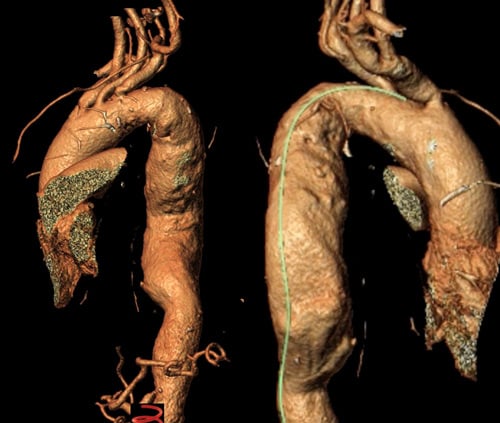

Distal optimisation and future treatment option

- Further extension of the 37 x 200 mm Gore® TAG® Conformable with a large diameter tapered 37/31 x 150 mm TAG® Conformable

- At the same time, preparation for a potential later extension into the abdominal aorta, should the disease progress and become treatment-indicated in this segment.

- Reduction of the risk of a distal stent graft–induced new entry (dSINE) and improved adaptation to the patient’s anatomy.

Patient-specific anatomical adaptation / distal optimisation and future treatment option

- Adaptation to the patient’s individual anatomy by extending the 37 mm TBE with an additional 37 mm TAG® Conformable with long overlap.

- Further extension of the 37 mm TAG® Conformable with Large Diameter Tapered TAG® Conformable to match the distal aortic diameter.